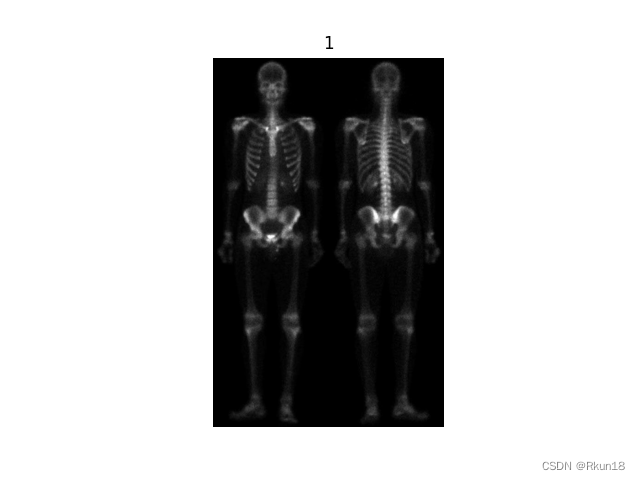

1:原始图像:

2:1拉普拉斯变化后:

图像全身骨骼扫描,图2为原始图像拉普拉斯变换后的结果,细节信息丰富,同时噪音变多。

上图更能直观地观察到图像变换后的差异。

文章介绍了混合图像增强技术在处理人体骨骼扫描图像中的应用,包括使用拉普拉斯变换增强细节,Sobel算子突出边缘,以及灰度幂律变换优化图像对比度。通过一系列图像处理步骤,实现了在保持细节的同时减少噪声并增强图像清晰度。